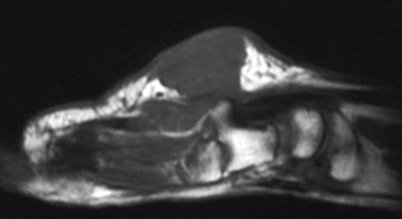

The preop MRI:

Click for larger image